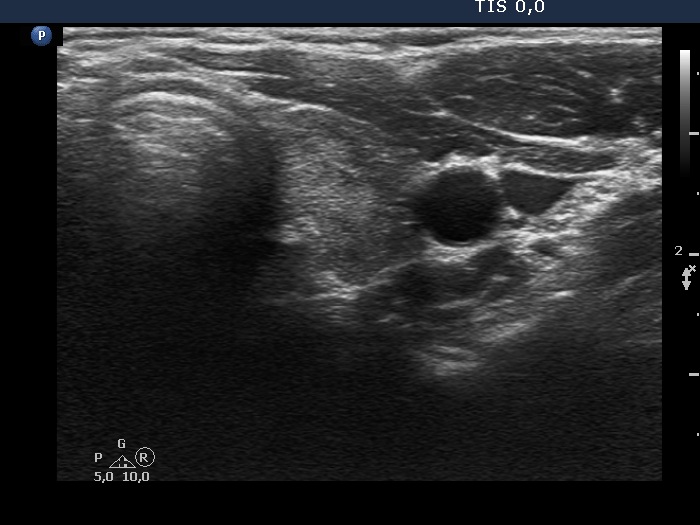

The borders of the nodule - case 2171 (ultrasonographic picture 5)

Right lobe, longitudinal scan